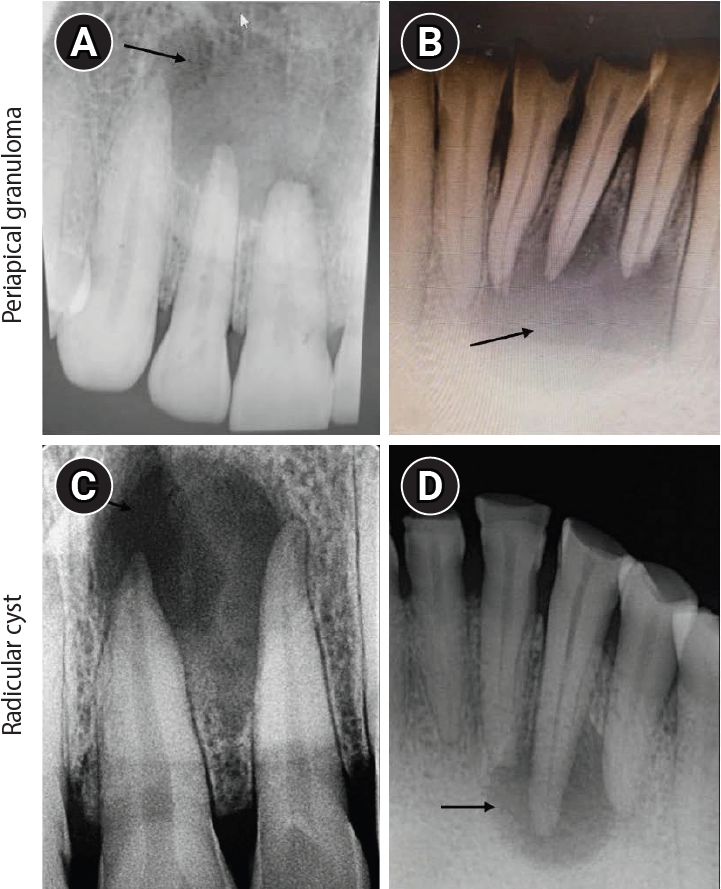

The study included a descriptive analysis of the immunohistochemical expression of HIF-1α, VEGF, and CD68 in 51 formalin-fixed, paraffin-embedded tissue sections comprising 17 cases each of HP, PG, and RC, obtained from prospective biopsy specimens received from May 2022 to May 2023. The criteria to include and exclude cases that determined the eligibility for participation in this study are outlined in Figure 1. Patient data, including age and sex, were obtained from biopsy records. Pathological diagnoses were confirmed based on clinical, radiographic, and histological criteria. HP tissue was obtained from extracted teeth that were free of caries and apical periodontitis, including those extracted for surgical indications such as third-molar removal. The pulp was immediately retrieved using a sterile high-speed fissure bur, and all cases were histopathologically confirmed as HP tissue. The study included human permanent, mature teeth from all quadrants. All selected specimens were periapical radiolucent lesions of varying sizes associated with non-vital pulp (Figure 2). PG consisted of granulomatous tissue with inflammatory cell infiltration, lacking an epithelial lining. RC was identified as fully developed cavities lined by stratified squamous epithelium of varying thickness with a fibrous wall [8].

Figure 2.

Intraoral periapical radiograph (IOPA) of periapical lesions. (A, B) IOPA of periapical granuloma cases showing well-defined radiolucency with respect to the maxillary right lateral incisor and mandibular right lateral incisor (arrows). (C, D) IOPA of radicular cyst cases showing well-defined radiolucency associated with the root apices of the maxillary left central incisor and mandibular right canine (arrows).